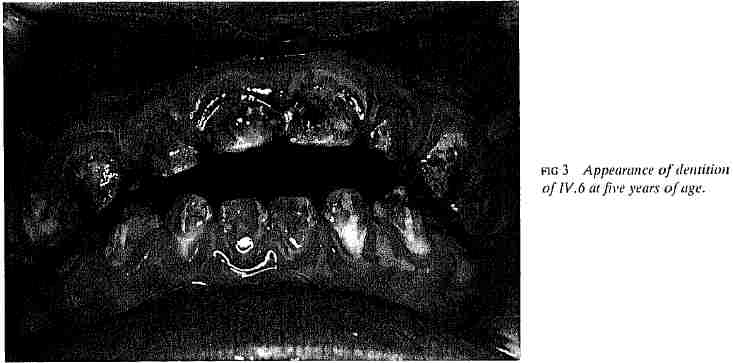

Die Zahnuntersuchung von IV.6 ergab die Diagnose des Syndroms in dieser Familie. Die ersten Zähne waren symmetrisch von Zahnschmelzdefekt und rauher Hypoplasie betroffen. Die Zähne hatten bedingt einerseits durch das durch den extrem dünnen Zahnschmelz scheinenden Dentin , andererseits durch Strukturveränderungen des Zahnschmelzes eine gelbliche Farbe. Abb. 2 zeigt eine Röntgenaufnahme des Gebisses von IV.6 im Alter von vier Jahren, und Abb.3 zeigt das Aussehen dieser Zähne im Alter von fünf Jahren.

Abb.3

Das Erscheinungsbild der Zähne von IV.6 im Alter von fünf Jahren.